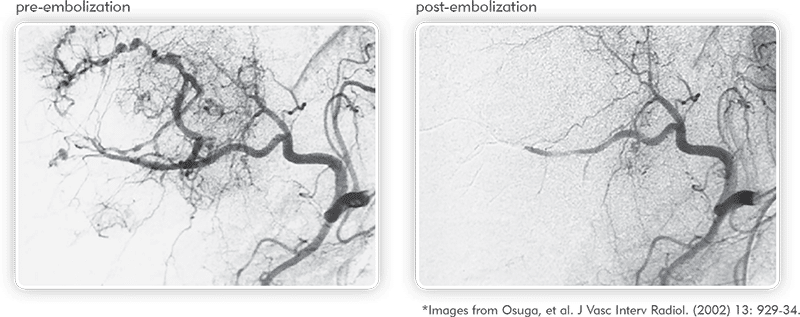

肿瘤血管成形术pré e pós-embolização图示电容成形术Microesferas QuadraSphere de realizar uma embolização direcionada